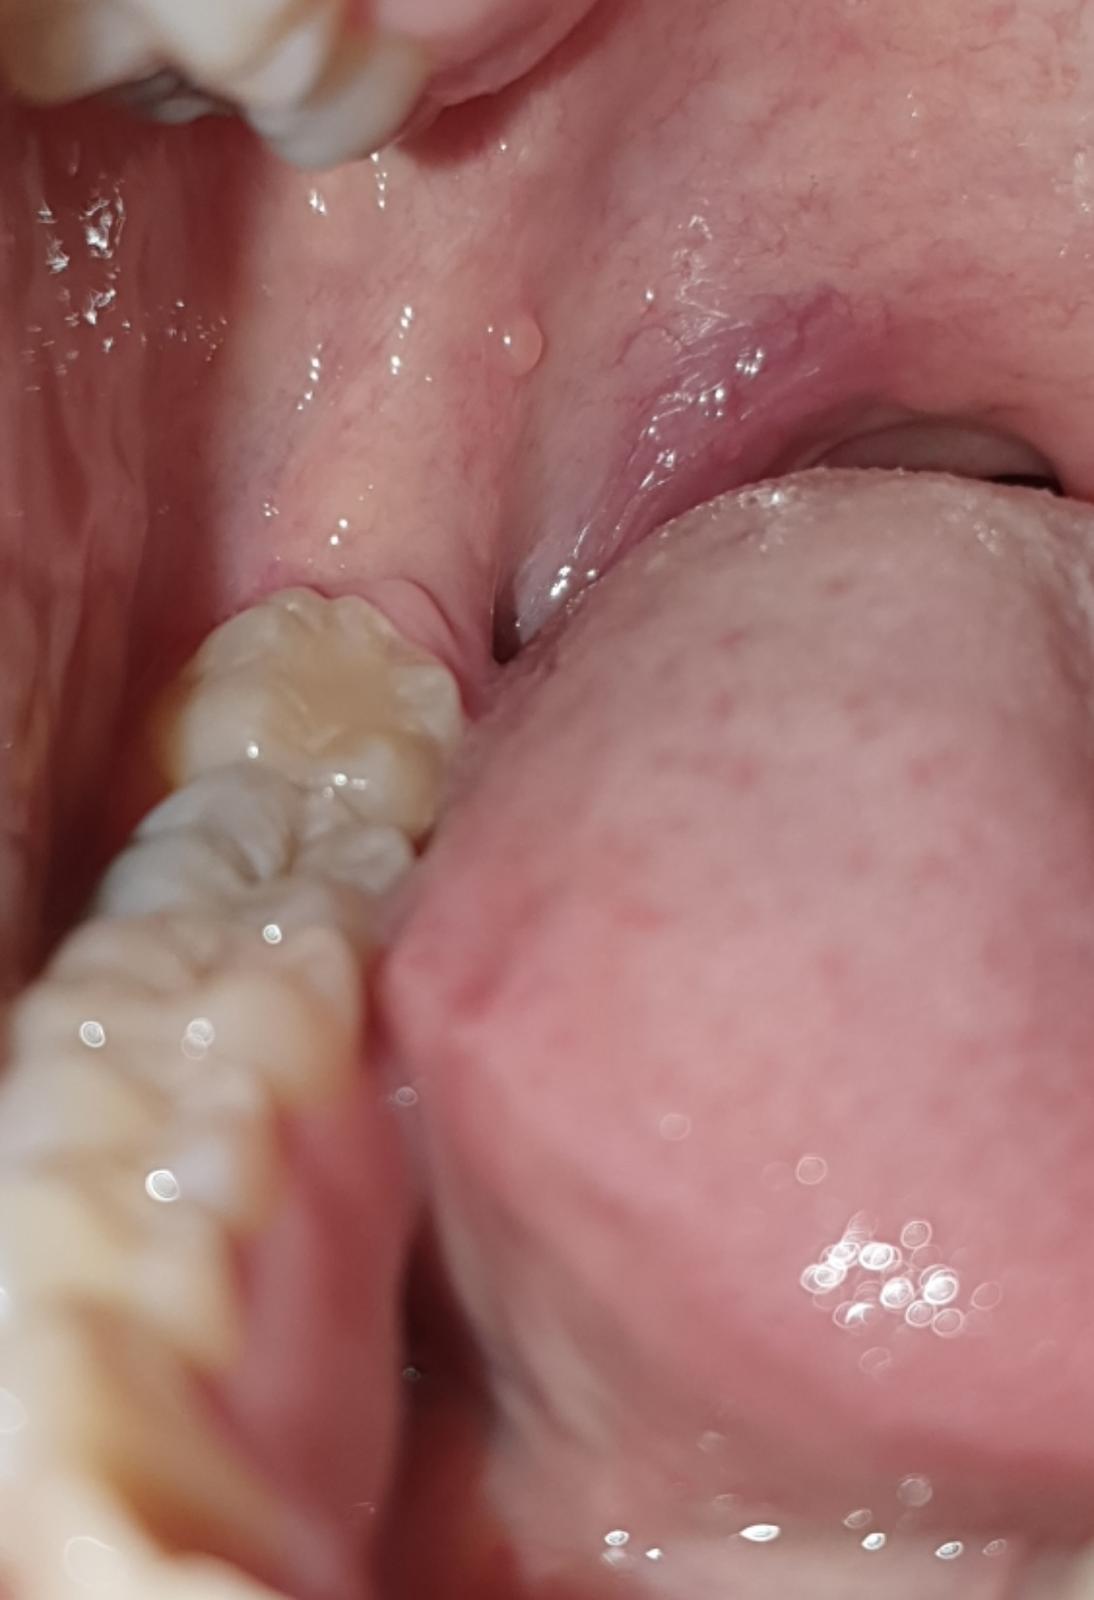

Pľuzgier v ústach

Ahojte, stretli ste sa s niečím takýmto ??

Pluzgier sa stále na tom istom mieste vytvorí, praskne a za pár dni zas narastie. Trvá to už dva mesiace.

Prikladám foto požičanú z netu